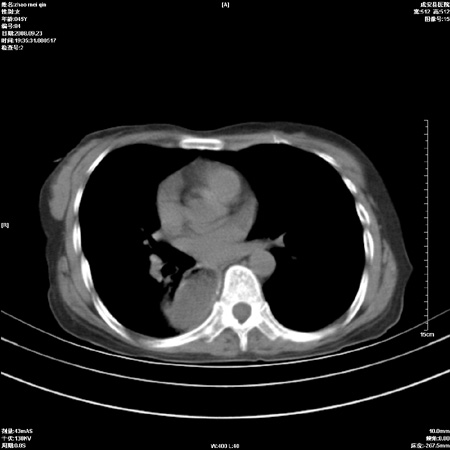

标题: CT15861:女 60 外伤后1小时 胸疼 [打印本页]

标题: CT15861:女 60 外伤后1小时 胸疼

外伤后1小时 胸疼 是外伤后引起的吗?

食道扩张明显下端逐渐变窄,倒像贲门失迟缓

考虑术后改变(胸腔胃),建议询问病史.

非外伤性改变,典型的贲门失迟缓症

食道扩张明显下端逐渐变窄,大量食物存留,象贲门失迟缓症。